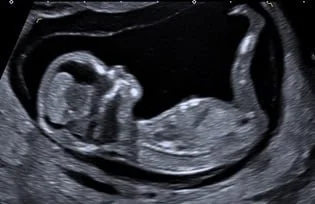

kombiniertes Ersttrimesterscreening mit Risikoberechnung für früh in der Schwangerschaft auftretende Bluthochdruckkomplikationen sowie die häufigsten Chromosomenstörungen beim Kind zwischen 11+0 – 13+6 SSW. Diese Untersuchung beinhaltet immer auch eine frühe Fehlbildungsdiagnostik des Kindes.

Feindiagnostik 19+0-21+6 SSW., erweitertes Organscreening des Kindes, Beurteilung der Plazenta, Fruchtwasser, Gebärmutterhals, Durchblutung

High-End-Ultraschall

Ich arbeite mit einem „High-End-Ultraschallgerät“ der neuesten Generation, welches speziell für Pränataldiagnostik und Frauenheilkunde entwickelt wurde.